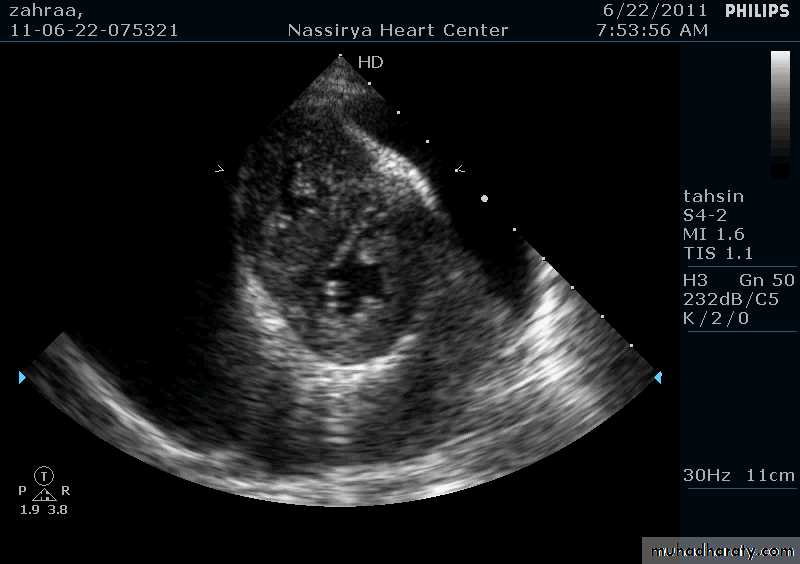

Pericardial Effusion: Investigation

Echocardiography: establishes the diagnosis31